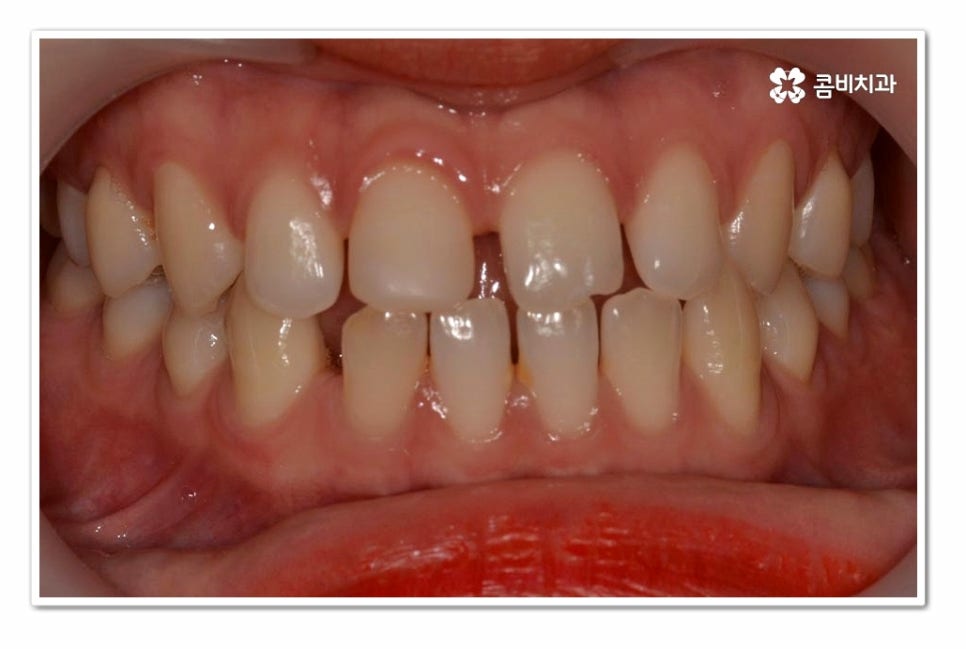

위 환자분의 경우 치아교정을 통해서 앞니 벌어짐 치료를 진행한 사례이며

치아의 이동 공간과 교합을 고려할 때 전체교정이 필요했던 사례라고 할 수 있어요.

위 환자분의 경우 윗니 만이 아니라 아랫니도 벌어져 있기 때문에

라미네이트와 같이 단기적으로 심미성을 고려한 치료보다는

치아교정을 통해 치아의 건강부터 교합, 심미성을 함께

개선할 수 있는 치료 계획을 세운 것이라 할 수 있어요.

오늘 보여드린 환자분의 케이스는 윗니와 아랫니가 모두 벌어져 있기 때문에

전체교정을 통해서 치료가 진행되었지만